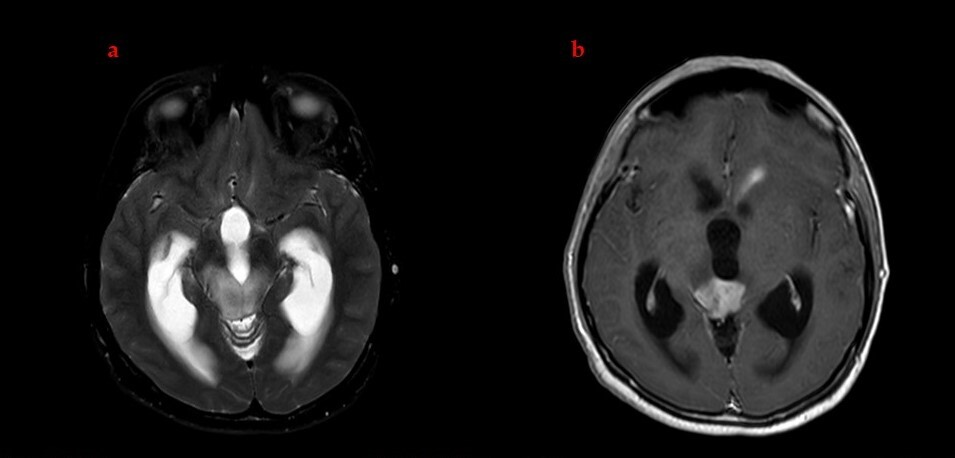

2.2. Definitive Chemoradiotherapy

2.3. Post-Treatment Complications